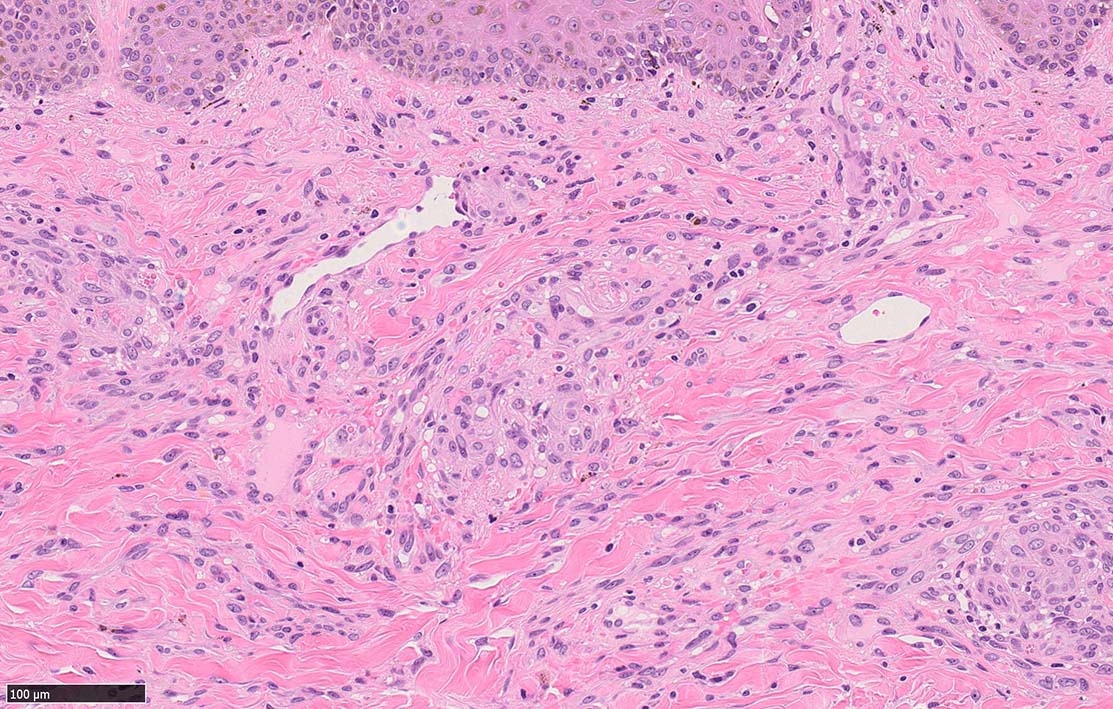

結節性病変の形成

紡錘形細胞が著しく増生し束状に走行する部分と, 内皮細胞様細胞による多数の小管腔構造が巣状にひろがり, 一見, 線維腫と血管腫が混在しているように見える. 一部の症例を除き, これらの増生細胞は異型性に乏しいことが多い.

細血管周囲に血管内皮様の紡錘形細胞が増生, 一部に赤血球をいれた裂隙の形成がある. 細胞の異型はみられず, mitosisの増多もない. hemosiderin-laden macrophageが散在する.

病変は真皮内に現局している. 初期斑状病変に相当すると考えられる. 本例では, 特徴とされる形質細胞浸潤増加はみられない.